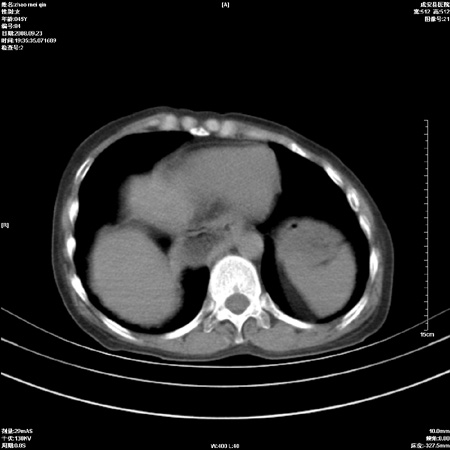

标题: CT15861:女 60 外伤后1小时 胸疼 [打印本页]

标题: CT15861:女 60 外伤后1小时 胸疼

外伤后1小时 胸疼 是外伤后引起的吗?

食道扩张明显下端逐渐变窄,倒像贲门失迟缓

非外伤性改变,典型的贲门失迟缓症

食道扩张明显下端逐渐变窄,大量食物存留,象贲门失迟缓症。